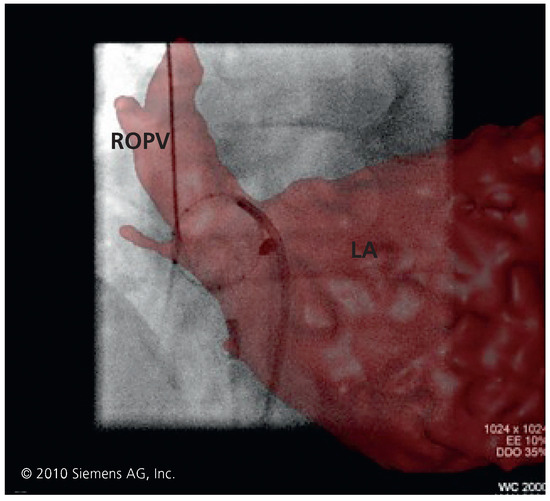

Moderne Technologien in der Ablation des Vorhofflimmerns

by Laurent M. Haegeli, Firat Duru and Thomas F. Lüscher

Cardiovasc. Med. 2010, 13(9), 272; https://doi.org/10.4414/cvm.2010.01529 - 15 Sep 2010

Modern technologies in catheter ablation for atrial fibrillation. Catheter ablation for atrial fibrillation has become an accepted therapy. The arrhythmia affects around 6% of the population over the age of 65 years. Electrical isolation of the pulmonary veins from the left atrium is the central strategy in catheter ablation for paroxysmal atrial fibrillation. However, procedural outcomes and efficacy using sequential “point-by-point” radiofrequency lesion creation with a conventional ablation catheter are operator-dependent and time-consuming. Moreover, reconduction across an initially complete lesion leads to recovery in electrical isolation of the pulmonary vein and recurrence of atrial fibrillation. New energy sources such as cryothermia, ultrasound and laser have emerged and are currently under investigation. These apply “single-shot” lesions via balloon mounted catheters positioned at the pulmonary vein ostia. Other new tools, such as magnetic navigation system and electromechanical robotic system, allow complete remote controlled mapping and ablation by combining three dimensional electroanatomical mapping. All these tools and technologies have to prove their effectiveness and safety. Full article

Show Figures

Figure 1